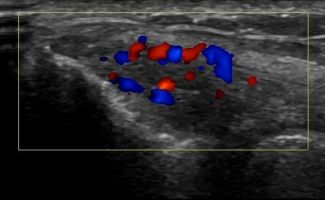

- Fluid collection in the bursa (i.e olecranon bursitis)

- Synovitis in the bursa as a symptom of Rheumatologic Disease